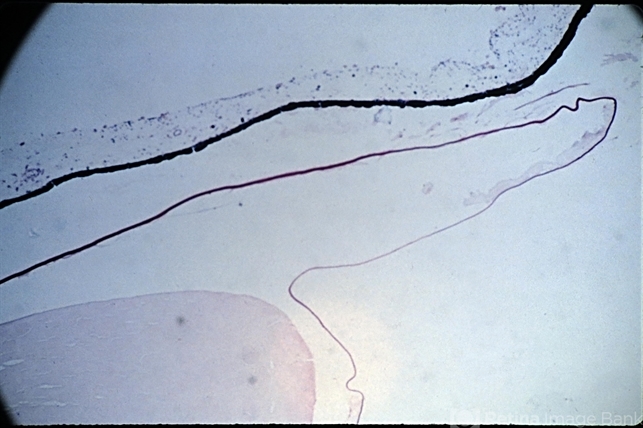

- Morgagni's cataract

- Morgagnian cataract. Nucleus remains within the capsule (x 16). The liquified cortex has been lost in preparation of the specimen. Note the loss of capsular epithelium. (Scheie Eye Institute, No. 3311.)